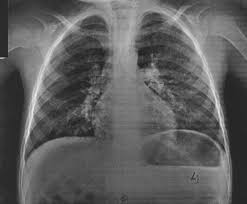

Las radiografías de tórax en pacientes con síndromes pulmonares eosinófilos suelen mostrar anomalías, pero estas no son específicas, lo que significa que las imágenes pueden evidenciar cambios que son consistentes con una variedad de trastornos pulmonares. Los infiltrados pulmonares visibles en las radiografías pueden variar en patrón y localización, y no hay una imagen radiográfica única que confirme de manera definitiva la presencia de eosinofilia pulmonar o su causa subyacente.

En la práctica clínica, la radiografía de tórax en estos casos puede mostrar infiltrados pulmonares, que son áreas opacas en el pulmón debido a la acumulación de células inflamatorias, fluidos o tejido anormal. Sin embargo, estos infiltrados son comunes en muchas enfermedades pulmonares, no solo en los síndromes eosinofílicos, y por lo tanto no permiten un diagnóstico específico. Esto implica que, aunque la radiografía puede ser útil para observar la extensión y la distribución de la enfermedad pulmonar, no puede distinguir entre diferentes tipos de eosinofilia pulmonar o determinar la causa precisa de los infiltrados.

Las radiografías de tórax en la neumonía eosinofílica crónica frecuentemente muestran infiltrados periféricos, que se describen a veces como el “negativo fotográfico” del edema pulmonar. En el edema pulmonar, los infiltrados tienden a ser más difusos y centrales, mientras que en la neumonía eosinofílica crónica, los infiltrados son más periféricos y pueden tener una distribución en parches. Este patrón radiográfico puede ayudar a diferenciar la neumonía eosinofílica crónica de otras condiciones pulmonares.